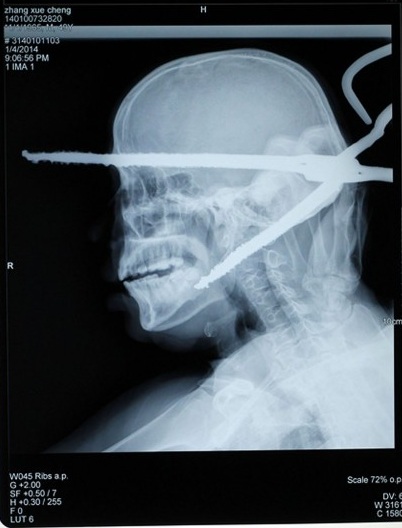

9) ¡WOW! Este hombre oriundo de China no podría tener más mala suerte… mientras caminaba hacia su casa, fue alcanzado por un par de tenazas que un vecino lanzó contra un perro callejero que le robó comida. Los médicos del hospital local lograron salvarle la vida.

Quirky China News | The Telegraph